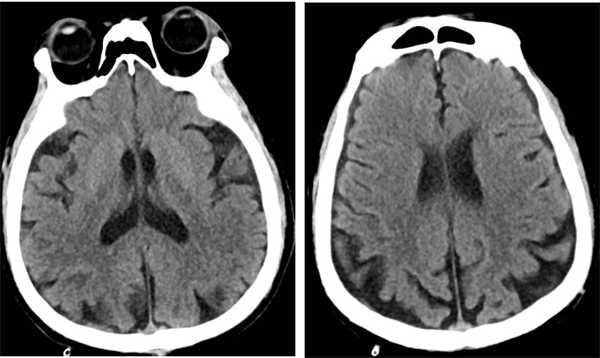

▲术后复查头颅CT

术后,何先生顺利苏醒,回到神经外科病房进行监护治疗,术后7天伤口愈合良好拆线出院。8月何先生来我院复查,DSA检查提示右侧颈动脉狭窄已完全恢复并无再狭窄,头晕及左侧肢体乏力症状也完全缓解了。